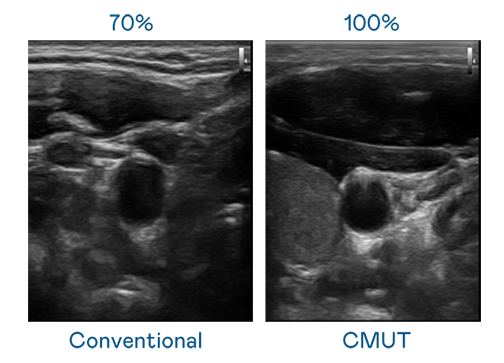

CMUT 技术是一种用电容式微机电元件来产生超音波讯号的技术。与传统 PZT 压电式技术相比,CMUT 频宽增加 30%,更宽频的超音波讯号让影像解析度大幅提升,是实现高影像品质医疗超音波扫描、促进精准医疗发展的关键技术。

大频宽带来超清晰影像

超音波影像的解析度高低,首先取决于探头能发出的讯号频宽。贝斯特 CMUT 可提供高清晰的超音波讯号,提供高频宽、高灵敏度、影像纹理细节更高的超音波影像,协助医护人员缩短影像判读时间及利用精准的医疗影像进行诊断。